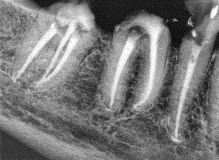

The New Frontier: Minimally Invasive Dentistry and Ozone Aerotherapy

FIGURE 13D--The post operative radiograph shows the root canal procedures completed, the coronal seals in place over the orifices and chamber floors in the molars and calcium hydroxide sealed in the chamber of the bicuspid.

In the early 1900’s, dental caries was considered “gangrene” of the teeth, which mandated nothing less than extraction. This radical treatment approach was replaced by the extension for prevention restorative concept introduced by Dr. Black and sophisticated by others throughout the twentieth century as the microbiological model of dental disease took hold. Known as macro-dentistry, … Read more